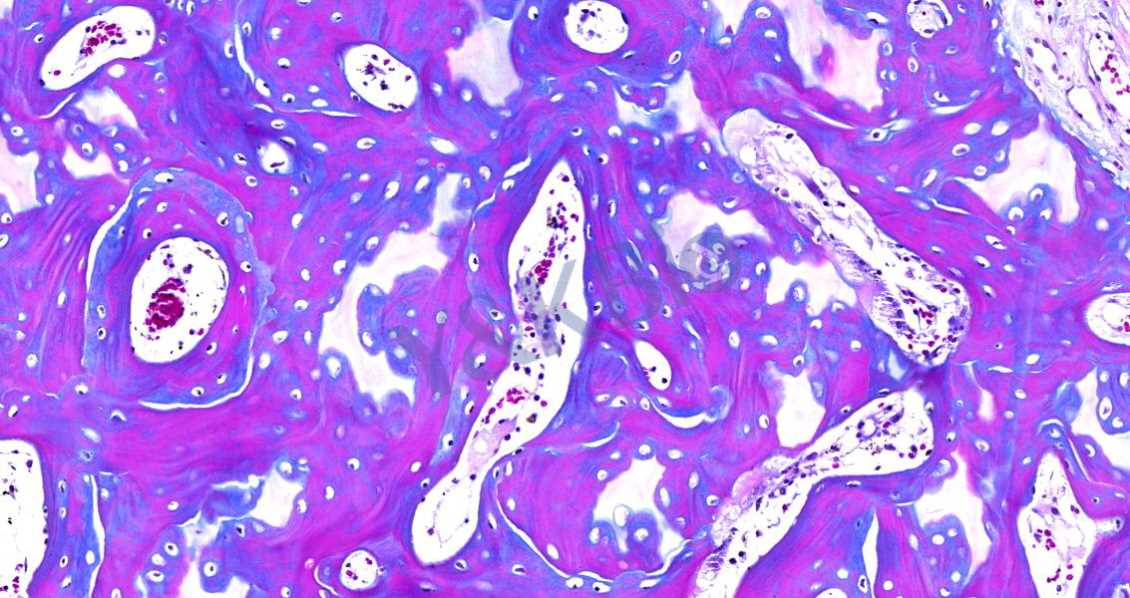

Masson染色的颜色对比鲜明,可见明显的胶原纤维网(吉林苯胺蓝染色则为蓝色,甲基绿则为绿色),能较好地反映纤维组织的形态。其中,蓝色表示新形成的骨,红色表示成熟的骨组织。

3.番红O-固绿染色

番红O-固绿染色可直观反映关节软骨、软骨下的骨组织结构,嗜碱性的软骨与碱性染料番红 O 结合呈现红色,嗜酸性的骨和酸性染料固绿结合而成蓝色,在关节软骨及软骨下骨的形态学研究中受到了欢迎。